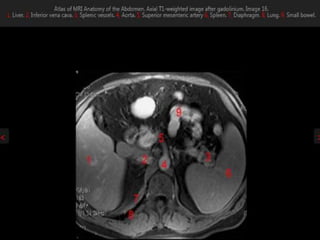

MRI anatomy images of the abdomen.

MRI anatomy imagesof the abdomen.